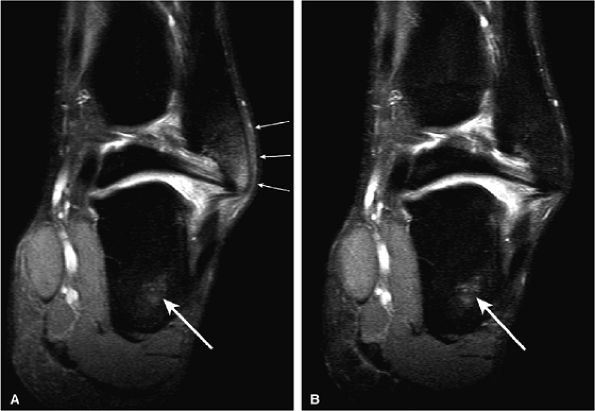

FIGURE 1.3 ● Total knee arthroplasty with synovitis (arrows). Acquired at 1.5 T. Use of an RBW of 83.3 kHz results in limited metallic susceptibility artifact.

FIGURE 1.4 ● Magic angle effect (arrows). (A, B) Magic angle is seen in a shoulder examination using a short TE (A) and long TE (B). Magic angle in an ankle examination without (C) and with (D) FatSat.